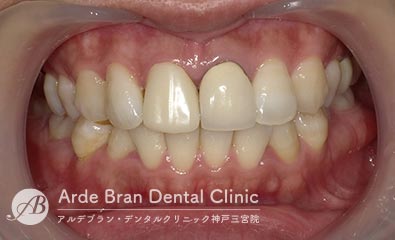

- ジルコニアセラミッククラウン(20代 女性 治療期間1カ月)

- 他院で入れた前歯の被せ物の形態や色調が隣の歯と合っていないため、やり替えたいとの事でご来院されました。切端に透明感があり、歯頚部から歯冠部にかけてグラデーションがある難しい歯でしたがトップテクニシャンとの連携により見事に再現する事が出来ました。

- 治療前

- 治療後

| 治療方法 | ジルコニアセラミッククラウンによる審美歯科治療 |

|---|---|

| 治療本数 | 2本 |

| 治療期間(通院回数) | 1カ月(4回) |

| 費用 | ジルコニアセラミッククラウン 24万円+TAX 仮歯 6千円+TAX |

| リスク副作用 | 審美歯科治療に関するリスクや副作用について、詳しくはこちらをご参照ください。 |